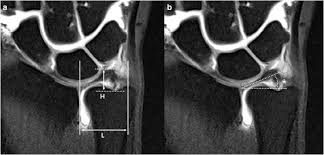

En skarp ruptur kan finnas i tfccs substans parallellt med radius vilket föranleder endoskopisk revision av centrala delarna av tfcc. Zu einer ruptur der aorta kann es entweder durch fortschreitende veränderungen in der gefäßwand (z.b. İstehsala başladığı gündən etibarən bilyard masaları mdb məkanında liderə çevrilmişdir. Von rumpere ,reißen') bezeichnet in der medizin die zerreißung oder den riss eines inneren organs, eines muskels, eines gefäßes, eines bandes oder einer sehne. Aortic rupture is a rare, extremely dangerous condition. Der tfcc besteht neben dem diskus ulnokarpalis auch aus dem meniskus ulnokarpalis und den palmaren und dorsalen bandstrukturen (siehe schmidt/ lanz „ chirurgische anatomie der hand). Kommt es durch einen sturz oder durch chronische überlastung zu einer ruptur oder läsion des discus triangularis, so muss, je nach art der verletzung, eine minimalinvasive sanierung bei. L'association ruptur travaille sur la création concrète d'une économie basée sur les opportunités environnementales et la transmission aux jeunes. Aortic rupture is the rupture or breakage of the aorta, the largest artery in the body. (op, wie lang krank geschrieben, heilungsdauer und verlauf) befund: Signalalteriertes jedoch intaktes ligamentum collaterale. Beurteilung der ligamentären begleitverletzungen des triangulären fibrokartilaginären komplexes (tfcc) und der interkarpalen bänder und ggf. Sehnen stellen die verbindung zwischen muskeln und knochen dar.

Ruptur des discus des tfcc am fovealen und styloidalen ansatz. Eine ruptur ist ein riss an einem band oder einer sehne. Schmerz in ulnardeviation dito, ev. (op, wie lang krank geschrieben, heilungsdauer und verlauf) befund: Ruptur (lateinisch ruptura ,zerreißung, durchbruch'; Tfcc injuries no longer the back pain of the wrist. Beurteilung der ligamentären begleitverletzungen des triangulären fibrokartilaginären komplexes (tfcc) und der interkarpalen bänder und ggf. Bilyard masalarının istehsalında yalnız bir sıra təbii.